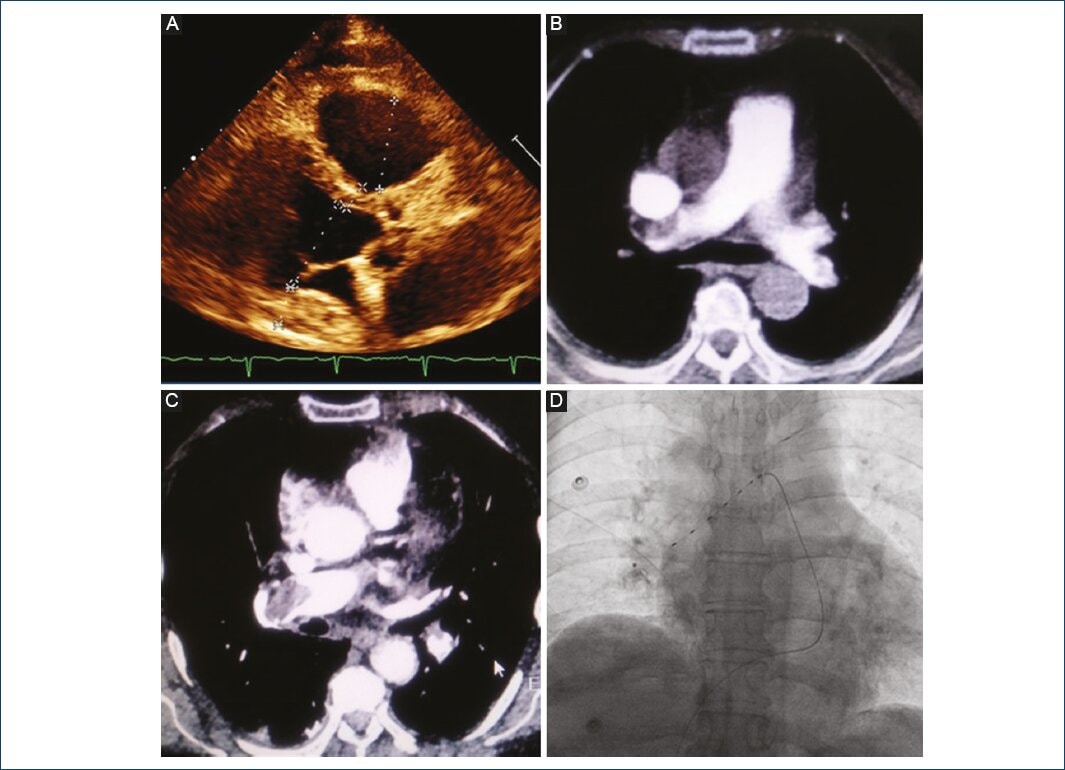

Reporte del caso

Paciente femenina de 78 años de edad, con antecedente de hipertensión arterial sistémica de larga data, así como un evento vascular cerebral isquémico 2 años antes, sin secuelas aparentes. Ingresó en el Servicio de Urgencias de nuestro centro por un cuadro de 6 minutos de duración de disnea súbita en reposo, acompañada de dolor precordial opresivo, diaforesis y náuseas. Bioquímicamente, presentaba elevación sérica de troponina I (130 pg/ml), y electrocardiográficamente, con infradesnivel del segmento ST en la pared inferior. Al examen físico se encontró somnolienta, presión arterial 95/60 mmHg, frecuencia cardíaca 130 lpm, frecuencia respiratoria 26 rpm, con saturación por oximetría de pulso de 82% al ambiente, ingurgitación yugular grado III, tórax simétrico sin estertores ni sibilancias, extremidades sin edema. Ecocardiograma transtorácico: VI con volumen telediastólico de 43 ml, volumen telesistólico de 21 ml, fracción de expulsión del 70%, sin alteraciones en la movilidad global o segmentarias en reposo; volumen auricular izquierdo de 30 ml/m2; válvula mitral sin regurgitación, válvula aúrtica trivalva, sin gradiente transvalvular significativo, sin insuficiencia; VD dilatado, con función sistólica severamente deprimida, desplazamiento sistólico del plano del anillo tricuspídeo (TAPSE) de 12 mm, onda S de 5 cm/s, fracción de acortamiento del 15%; aurícula derecha dilatada, sin trombos en su interior; válvula tricúspide estructuralmente normal, con déficit de coaptación que genera jet concéntrico de insuficiencia moderada, vena contracta de 5 mm, gradiente de regurgitación de 75 mmHg; se calcula una presión sistólica de la arteria pulmonar (PSAP) de 85 mmHg, proporción VD/VI de 0.98 (Fig. 1A). Se procede a realizar angiotomografía pulmonar en la que se encuentra el VD dilatado, proporción VD/VI de 0.99, así como defecto de llenado con oclusión total distal en la rama principal derecha de la arteria pulmonar (Figs. 1 B y C), lo que confirma el diagnostico de tromboembolismo pulmonar agudo submasivo (PESI score en clase V, de muy alto riesgo, mortalidad asociada del 10-24% en 30 días).

Figura 1 Fase diagnóstica de tromboembolia pulmonar y tratamiento. A: ecocardiograma transtorácico inicial, eje paraesternal largo, en el cual se observa dilatación del VD, proporción VD/VI de 0.98. B: angiotomografía pulmonar en corte axial, con defecto de llenado en la rama derecha de la arteria pulmonar que se extiende a ramas subsegmentarias. C: corte axial a nivel de T5 con mayor definición del defecto de llenado de la rama pulmonar derecha. D: resultado fluoroscópico final con sonda EKOS (BTG-IM, Bothell, Washington), colocada desde el segmento distal de la arteria lobar inferior derecha hasta la bifurcación del tronco pulmonar.

Durante el mismo procedimiento se colocó una sonda EKOS Endovascular System (BTG-IM, Bothell, Washington) de la siguiente manera: mediante un introductor 6 French venoso en la vena femoral derecha, se procedió a avanzar una guía hidrofólica 0.035, a través de la cual se avanzó un catéter con curva multipropósito 5 Fr para realizar las mediciones de las cavidades anteriormente comentadas. Posteriormente, se realizó la angiografía pulmonar, ya comentada. Basándose en los hallazgos se avanzó la guía hidrofóica hacia la rama derecha y, despuús, a la arteria lobar inferior derecha; se hace un intercambio por la sonda EKOS y se deja colocada desde el segmento distal hasta la bifurcación del tronco pulmonar (Fig. 1 D); se corrobora el adecuado funcionamiento de la consola y la adecuada infusión de fármaco y refrigerante, dando por terminado el procedimiento, sin complicaciones.